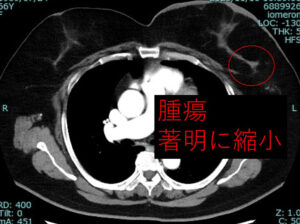

と、いうことで結局当院へ転院術前抗がん剤(phesgo+docetaxel)を施行してつい最近手術しました。

効いたねー!

術前抗がん剤後 腫瘍著明に改善 皮膚浮腫の範囲も縮小

リンパ節も、かなり効いています。